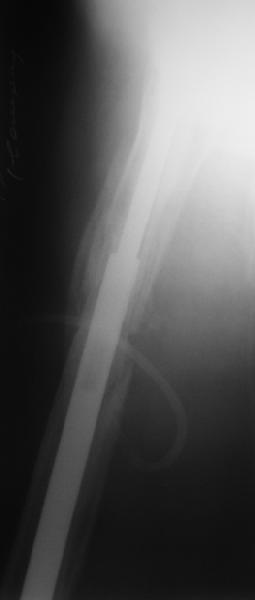

Спасибо за обсуждение. После нескольких дней тракции аппаратом сделали. Попытка закрытой репозиции не удалась из-за смещения по ширине, мешали фрагменты цемента. После их удаления репозиция получилась. Еще убрали немного цемента с ножки по латерльной стороне, чтобы обнажить 40-50 мм ее дистальной части, для плотной посадки гвоздя. Дальнейшее введение гвоздя было несложным. Протез показался нам стабильным в проксимальной части как латерально, так и медиально. Картинки в приложении.

THX for the discussion. After few days of traction by ex-fix the surgery was performed. An attempt of closed nailing was unsuccesful because of fragment translation, which was blocked by cement fragments. After removal of broken cement pieces reduction was reached "automagically". Also some cement from lateral part was removed by

chisel to expose distal 40-50 mm of the stem to allow tight fit of the nail. Further fixation by the nail was pretty easy and straightforward. Images attached. The stem looked stable in its proximal part both laterally and medially. Comments/critics are welcome.